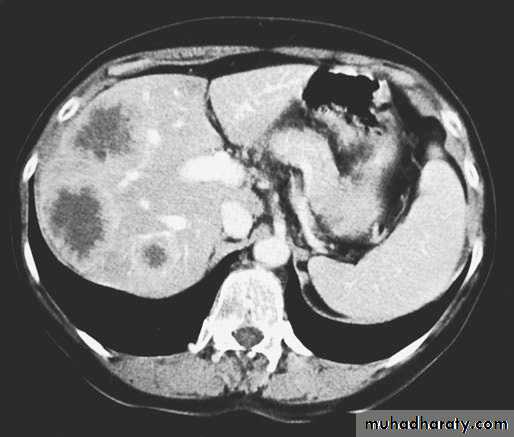

1.CT scan for hematogenous spread and distant metastasis.

Figure4: CT scan showing liver metastasis.